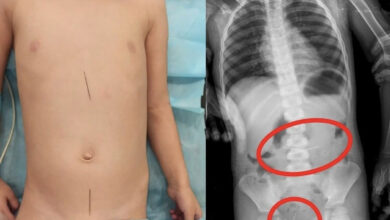

Таразда дәрігерлер төрт тігін инесін жұтып қойған баланы құтқарып қалды

Жамбыл облыстық көпбейінді балалар ауруханасына 3 жастағы баланың анасы оның киімдегі «молния» ілгегінің жүгіртпесін жұтып қойғаны туралы шағымданып, баланы ауруханаға…